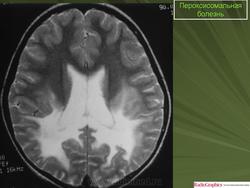

ГМ. Пероксисомальная болезнь. +

Пероксисомальная болезнь.